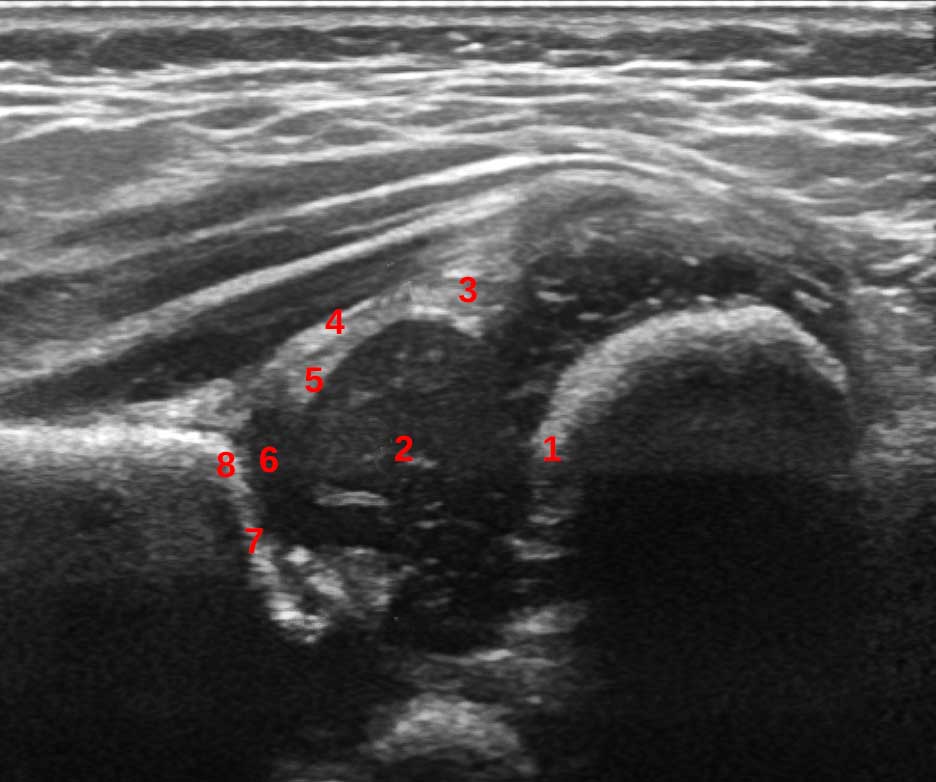

1. The chondro-osseous border

2. Femoral head

3. Synovial fold

4. Joint capsule

5. Labrum

6. Cartilage

7. Bony roof

8. Turning point - the point where the bony roof turns from convexity to concavity

Further anatomical structures are:

1. Proximal perichondrium (Tendon of reflected head of rectus femoris, perichondrium of hyaline cartilage, and joint capsule fat deposit)

2. Perichondrial gap (distal capsule and perichondrium), ischio-femoral ligament

3. Triradiate cartilage

4. Ligamentum teres

5. Ischium

6. Greater trochanter

7. Gluteus minimus

8. Gluteus maximus

9. Intermusular septum

10. Femoral metaphysis